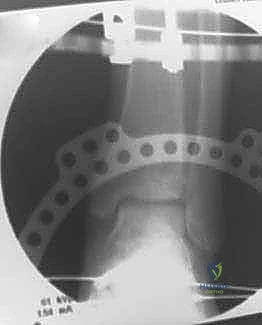

الخطوة الثانية: تركيب الإطار الخارجي (Ilizarov Frame)

هذه هي المرحلة الهندسية الدقيقة. يتم تركيب حلقتين معدنيتين حول عظمة الساق (Tibia) وحلقة ثالثة حول القدم (تثبت في عظمة العقب Talus وعظام مشط القدم).

الخطوة الثالثة: إدخال الأسلاك والمسامير (Wire and Pin Placement)

يتم تمرير أسلاك معدنية رفيعة جداً (Kirschner wires) ومسامير نصفية (Half-pins) عبر العظام لتثبيت الحلقات. يعتمد الأستاذ الدكتور محمد هطيف على معرفته التشريحية العميقة واستخدام جهاز الأشعة المرئي (C-arm) لضمان مرور هذه الأسلاك في "الممرات الآمنة" (Safe corridors) بعيداً عن الشرايين والأعصاب الحيوية.

الخطوة الرابعة: تركيب المفاصل الصناعية (Hinges)

هنا يكمن السر الأكبر للنجاح. يتم توصيل حلقة الساق بحلقة القدم باستخدام مفاصل معدنية قابلة للحركة (Hinges). يجب أن يتم وضع محور هذه المفاصل المعدنية ليتطابق تماماً مع المحور التشريحي الطبيعي لدوران مفصل الكاحل (Center of Rotation of the Talus). هذه الدقة تضمن إمكانية تحريك الكاحل أثناء فترة العلاج دون إحداث ضغط غير متساوٍ على الغضروف.

الخطوة الخامسة: تطبيق التشتيت (Distraction)

أثناء العملية، يقوم الدكتور هطيف بإبعاد حلقة الساق عن حلقة القدم تدريجياً وببطء باستخدام قضبان ملولبة، حتى يصل إلى مسافة تشتيت تبلغ حوالي 5 إلى 6 ملليمترات. يتم التأكد من هذه المسافة عبر الأشعة السينية داخل غرفة العمليات.

فترة العلاج والتأهيل: 12 أسبوعاً من إعادة البناء البيولوجي

بعد نجاح العملية، تبدأ مرحلة لا تقل أهمية، وهي فترة بقاء الإطار المعدني على الساق، والتي تستمر عادة لمدة 10 إلى 12 أسبوعاً (حوالي 3 أشهر). يتابع الأستاذ الدكتور محمد هطيف مرضاه عن كثب خلال هذه الفترة لضمان سير العملية البيولوجية بنجاح.